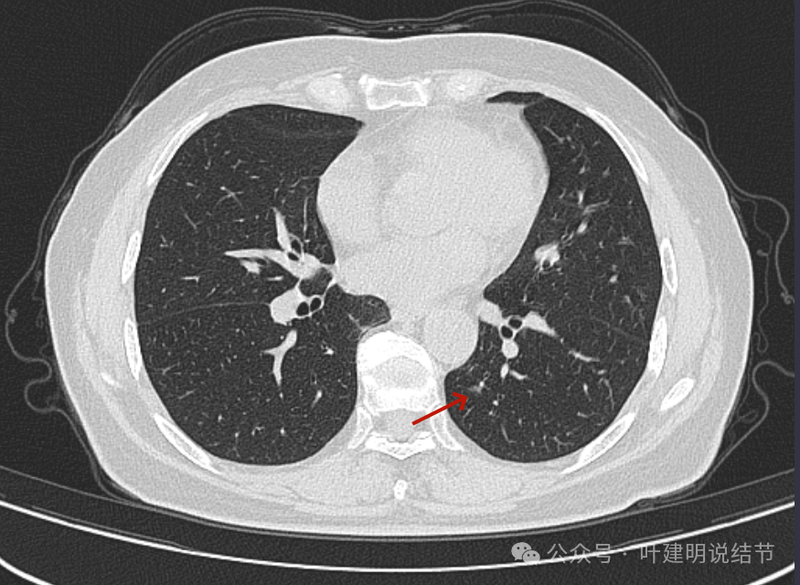

病灶出现,磨玻璃密度,略有偏实性成分,整体轮廓与边界较为清楚。